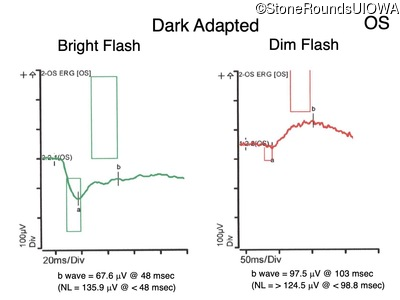

Congenital Stationary Synaptic Dysfunction (IA2g)

Congenital Stationary Synaptic Dysfunction (IA2g)

| Congenital Stationary Synaptic Dysfunction | CABP4 | Arg49Stop CGA>TGA | IVS1+1 G>T | AR |